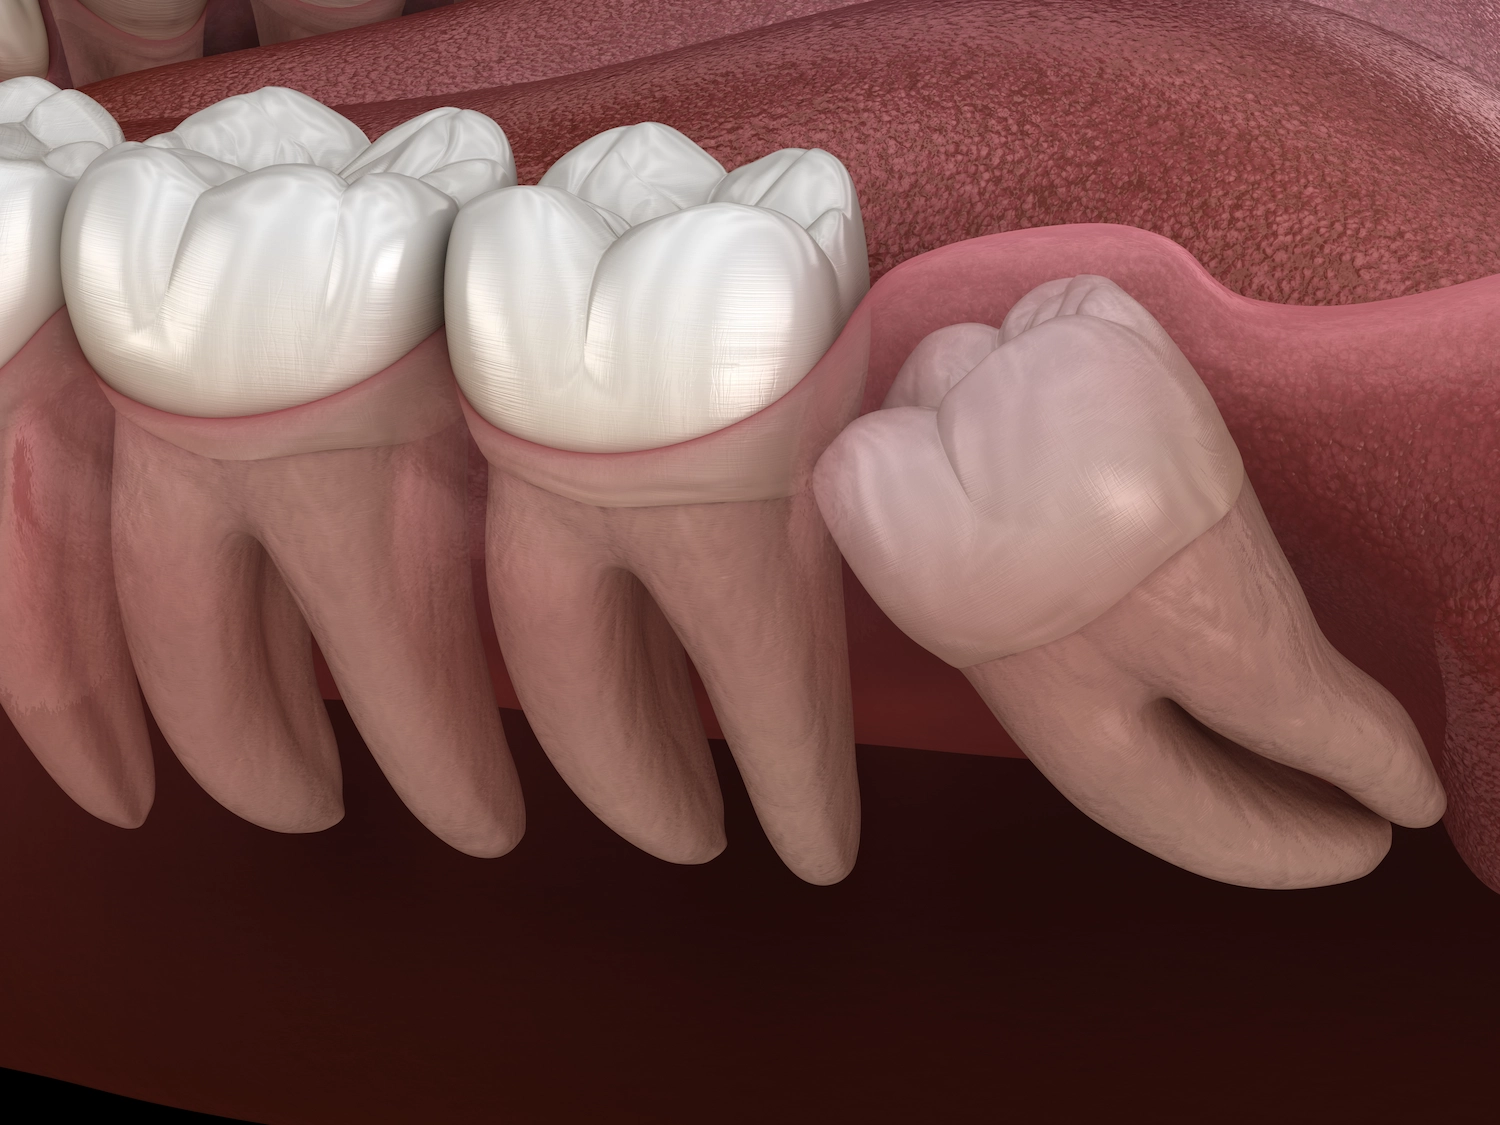

Entfernung von Weisheitszähnen

Wir schaffen Platz im Kiefer und sorgen für die dauerhafte Stabilität Ihrer Zahnreihen.

Eine präzise Voruntersuchung ist die Grundlage für den Erfolg jeder Behandlung. Wir nutzen moderne bildgebende Verfahren, wie zum Beispiel dreidimensionale Röntgenaufnahmen, um empfindliche Bereiche wie Nervenverläufe oder benachbarte Zähne bestmöglich zu Schützen. Gemeinsam mit Ihnen entscheiden wir, welches Vorgehen für Ihre Situation am sinnvollsten ist, und klären Sie transparent über alle Möglichkeiten auf.